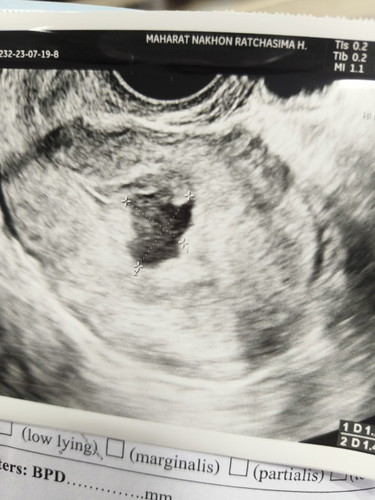

ถุงตั้งครรภ์ผิดรูปไม่เจอตัวอ่อน 8W5d

มีใครเป็นแบบเราบ้างไหมค่ะ ถุงตั้งครรภ์ไม่สวย ซาวด์ก็ไม่เจอน้อง ซางทั้งช่องคลอดและหน้าท้อง ครรภ์ 8W5d #เราเคลียดมากตอนนี้ ท้องนี้ท้องที่ 3 ท้องที่สองก็พึ่งแท้งไปครบปีพอดี ท้องนี้จะแท้งอีกไหมค่ะ